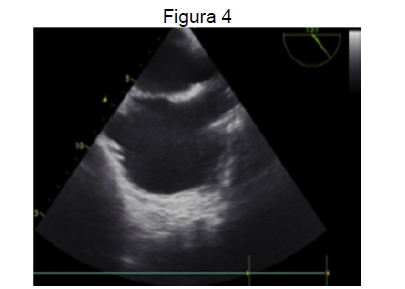

Fonte: Consenso Sobre Ecocardiografia Transesofágica Perioperatória da Sociedade Brasileira de Anestesiologia e do Departamento de Imagem Cardiovascular da Sociedade Brasileira de Cardiologia

Sobre o ecocardiograma transesofágico, considerando a figura 4, analise as assertivas e identifique com V as verdadeiras e com F as falsas.

( ) No corte bicaval, pode-se avaliar a porção superior do septo atrial.

( ) Câncer esofagiano é uma contraindicação para realização do exame.

( ) A incidência quatro câmaras é ideal para avaliar trombos em ápice de ventrículo esquerdo.

( ) A incidência basal de eixo curto a, aproximadamente, 45 graus pode avaliar o apêndice atrial esquerdo.

( ) O corte da figura 4 pode ser útil para investigação de trombos em portadores de cateteres de hemodiálise.

A alternativa que contém a sequência correta, de cima para baixo, é